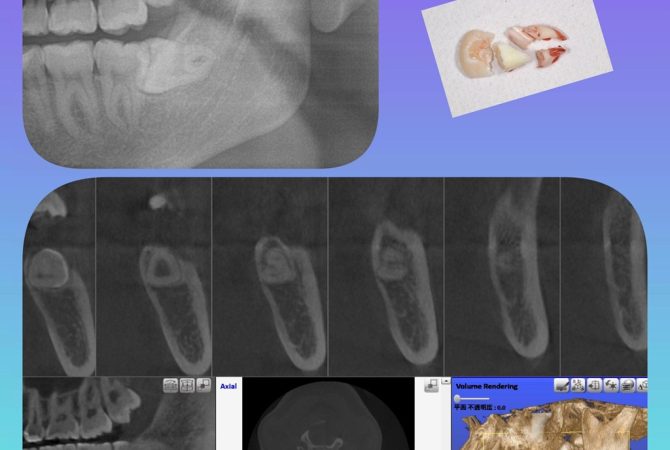

2025.12.10 症例 横向き親知らずの抜歯症例 詳しく見る 2025.12.4 症例 EMS社エアフローを使用した定期検診症例 詳しく見る 2025.11.18 症例 EMS社エアフローを使用した定期検診症例 詳しく見る 2025.11.14 症例 EMS社エアフローを使用した定期検診症例 詳しく見る 2025.11.12 症例 横向き親知らずの抜歯症例 詳しく見る 2025.10.19 症例 拡大床と3DLによる小児矯正症例 詳しく見る 2025.10.14 症例 横向き親知らずの抜歯症例 詳しく見る 2025.10.4 症例 横向き親知らずの抜歯症例 詳しく見る 2025.9.22 症例 横向き親知らずの抜歯症例 詳しく見る 1 / 7 ページ23…7次へ »